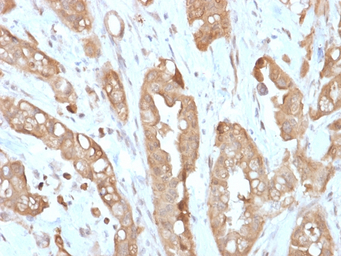

IHC-P analysis of human small intestine tissue section using GTX02740 Villin antibody [VIL1/2310R].